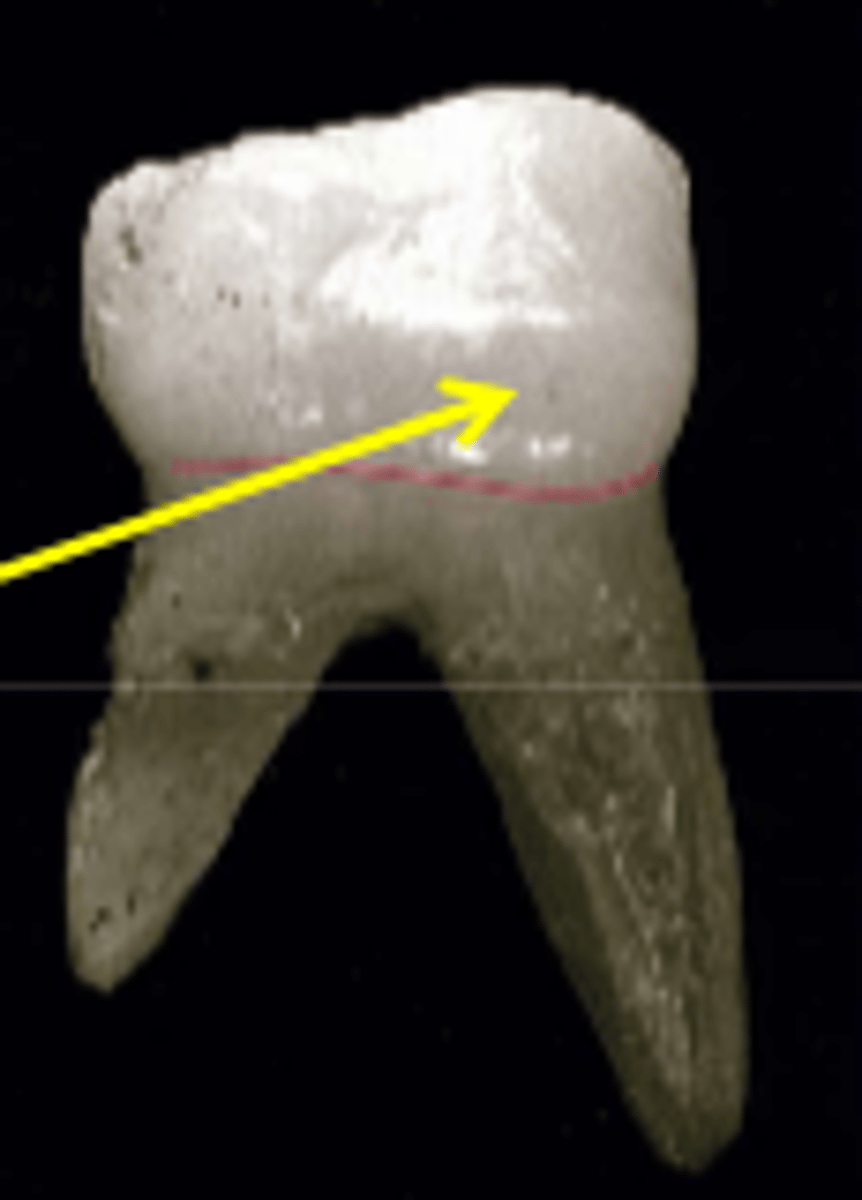

What is the cervix of the root?

constricted region surrounding the junction of the crown and root

What is the root trunk?

portion of multirooted tooth that is not split or furcated

What is furcation?

portion of multirooted teeth that is split into multiple roots

What is the furcal region?

the space between two or more roots